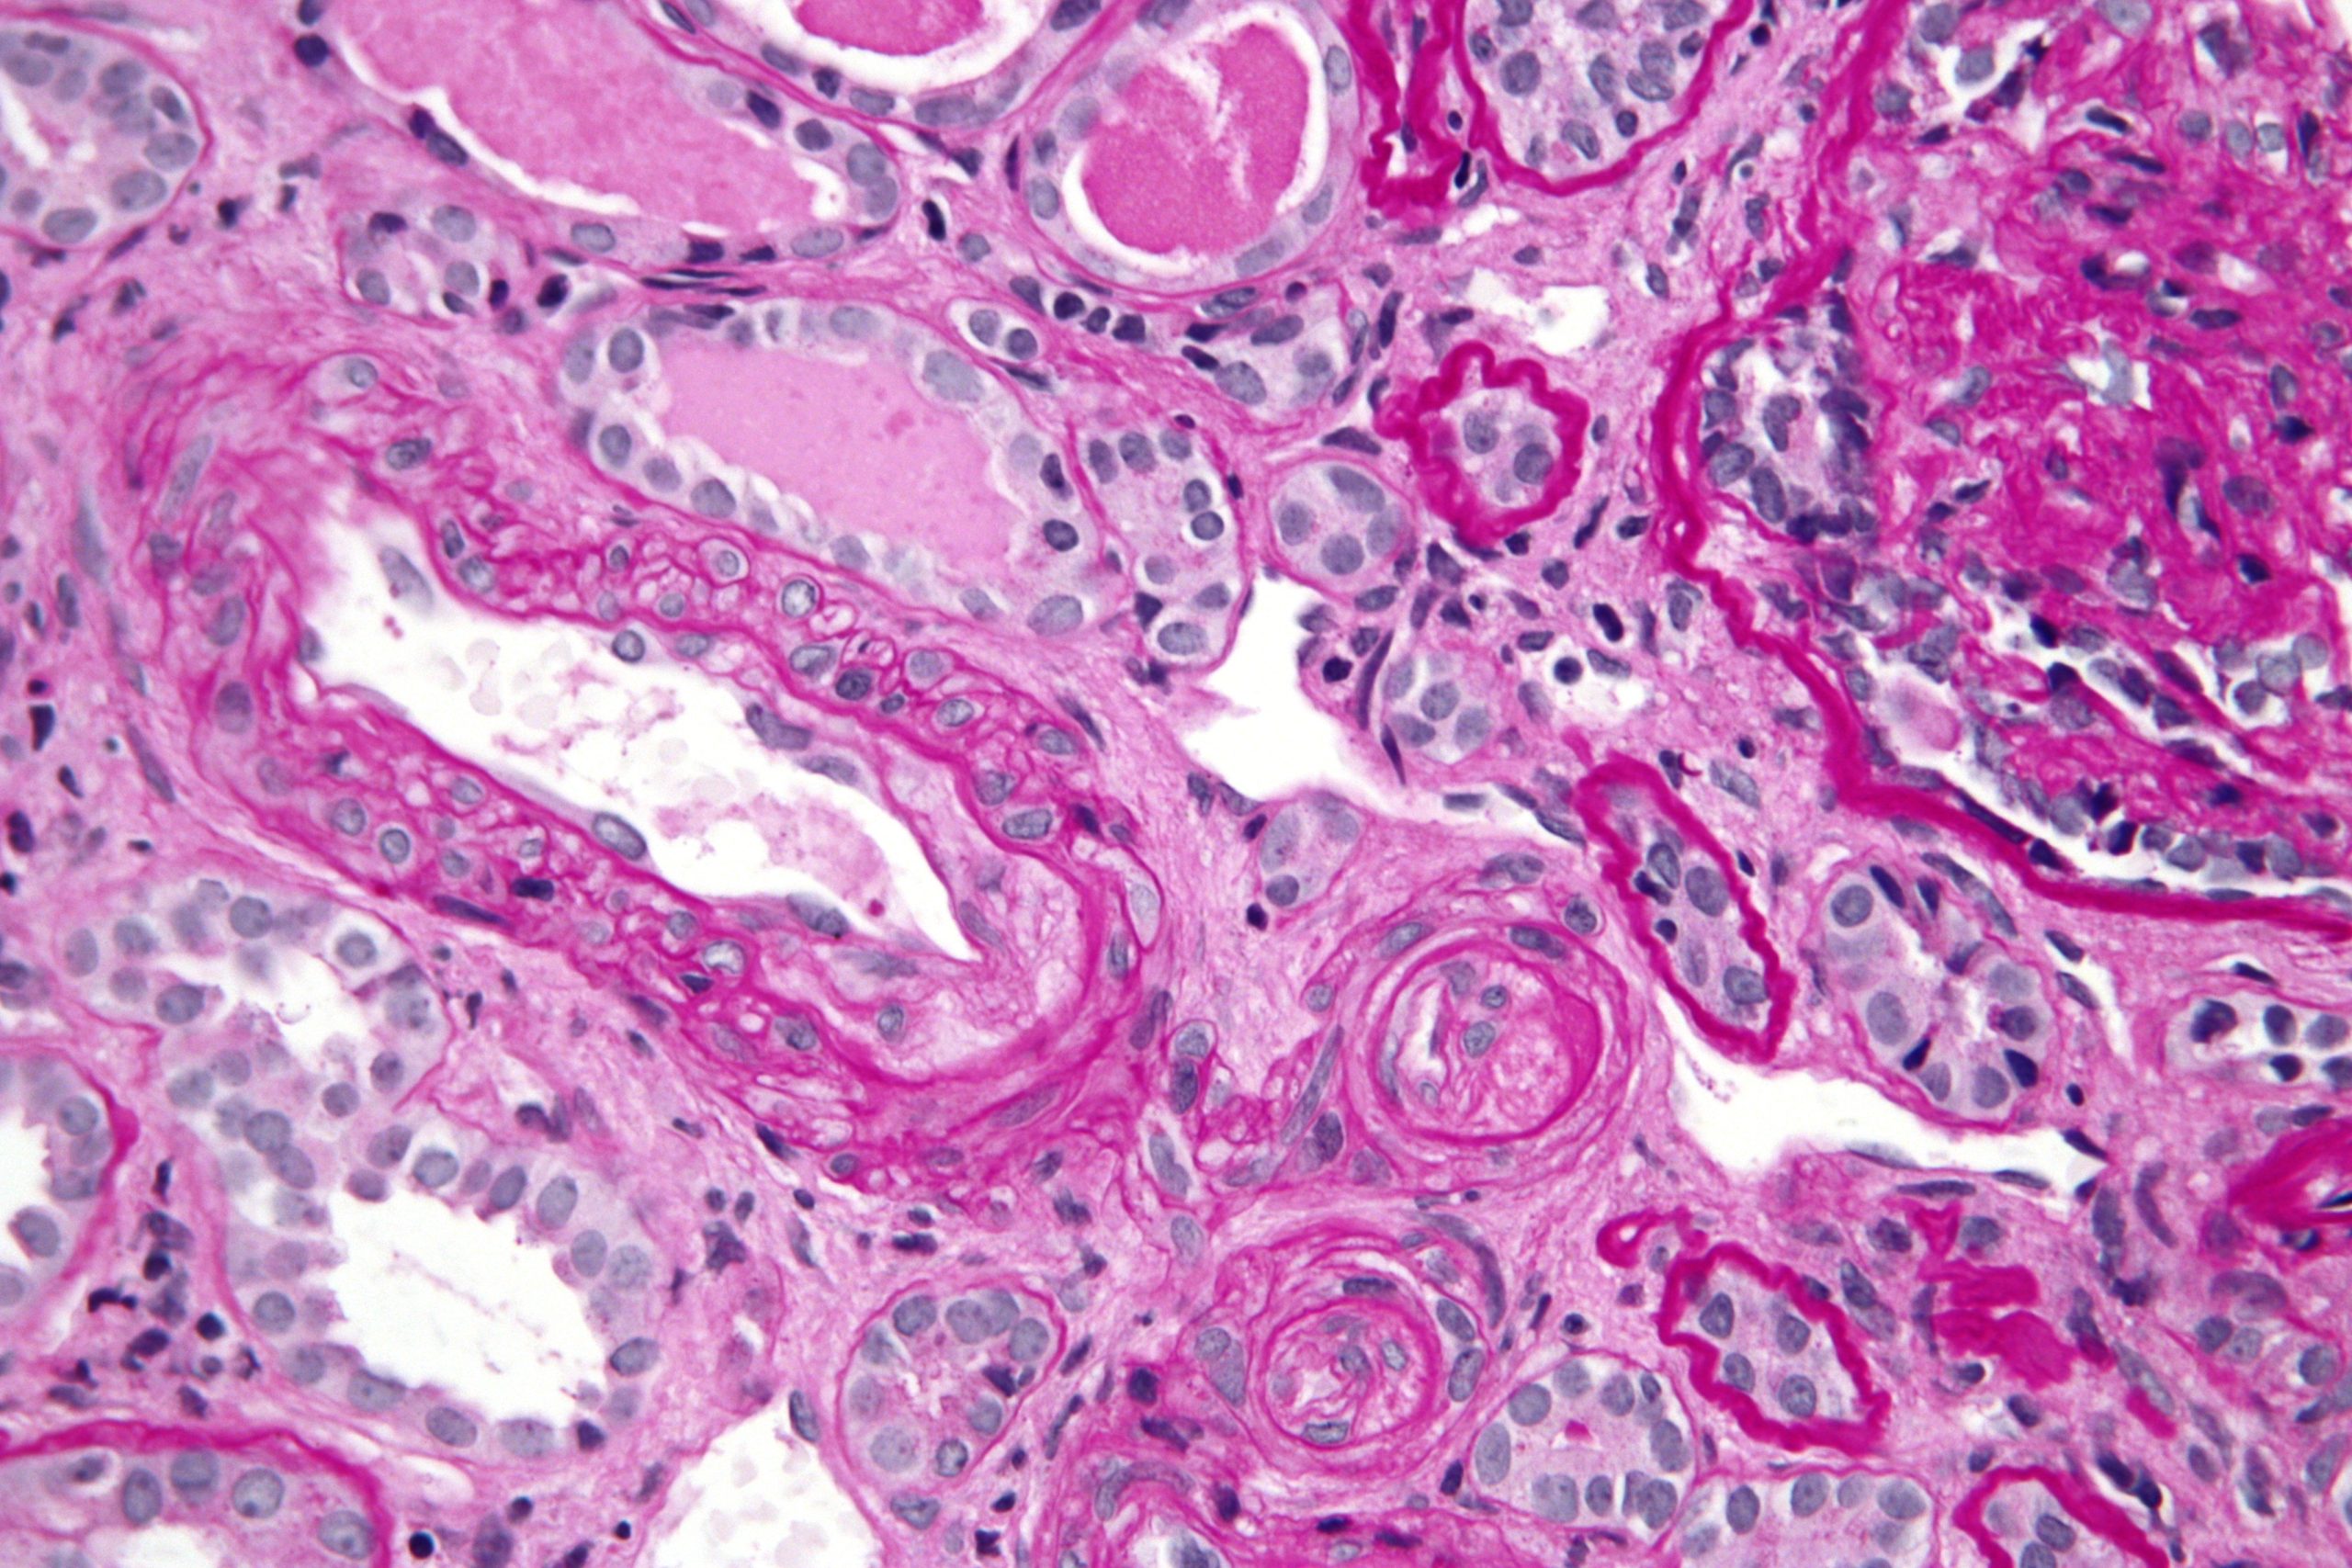

Thrombotic Microangiopathy

One of the biggest issues in early xenotransplantation was thrombotic microangiopathy. It is the development of multiple clots in small blood vessels of the organ, leading to ischaemia and death of the tissue.

The solution has been twofold:

Thrombosis and Coagulation

Thrombotic microangiopathy remains one of the toughest issues. Pig‑human blood‑clotting systems are not perfectly aligned, so:

- Microclots form in small vessels inside the graft.

- Over time, these clots block blood flow and cause organ failure.

Solutions now include:

- Genetic insertion of human-like clot-regulating genes (thrombomodulin, EPCR, CD47).

- Careful use of anticoagulant drugs around the transplant window.

These interventions have significantly reduced early clotting-related failures in recent xenotransplants.